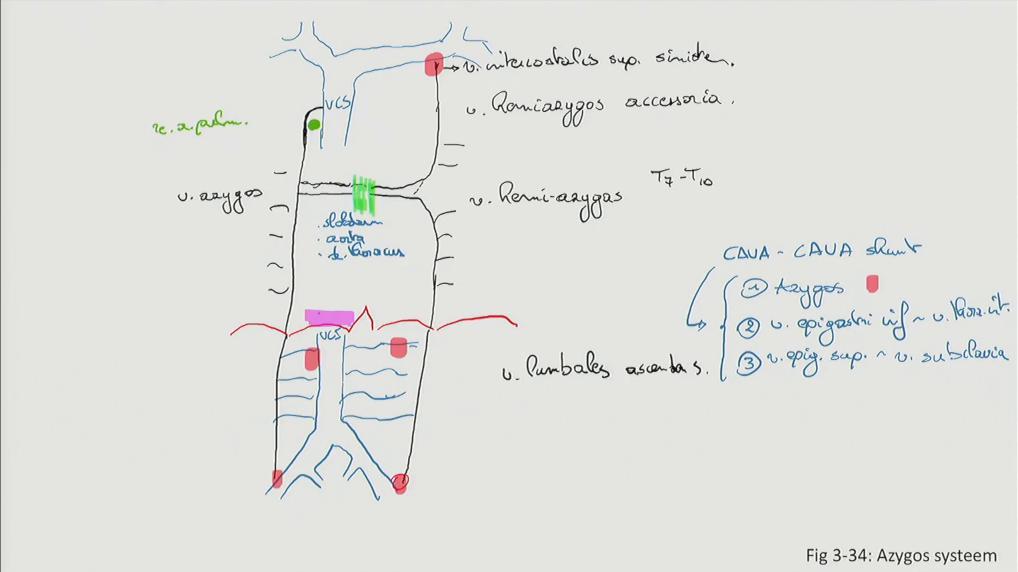

Fig 3.34: Azygos systeem

|

Sobotta: Fig 2.121